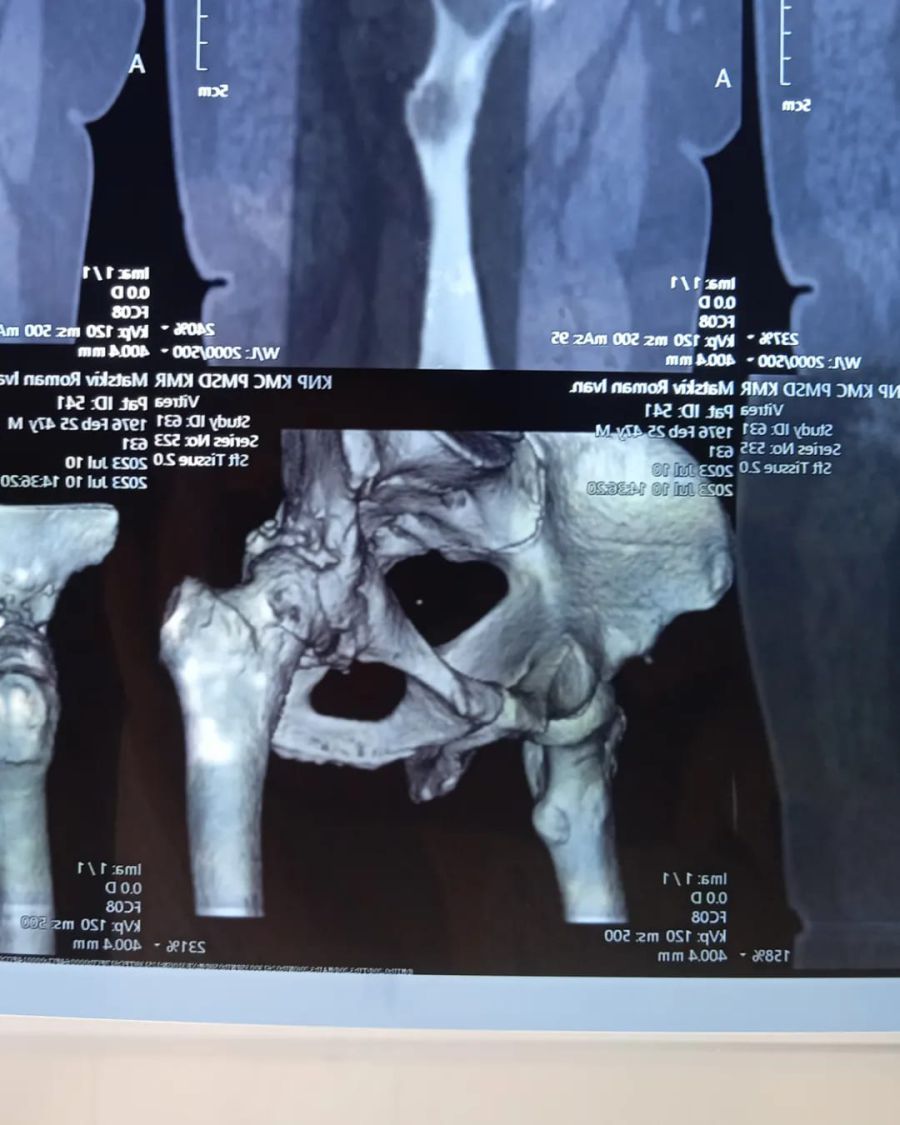

"В нашій сім'ї сталася прикра ситуація. В мого батька, Мацьків Романа, діагностувати лівобічний коксартроз IV стадії та правобічний коксартроз II стадії. Це дегенеративно-дистрофічне захворювання, при якому руйнуються хрящі, що покривають поверхню голівки стегна і вертлюжної западини. Ліва нога стала коротша на 3 сантиметра", — йдеться в повідомленні.

"Лікар сказав, що праву ногу ще можливо лікувати, і в цьому є сенс. А от ліва нога потребує ендопротезування і ,бажано, якнайшвидше, поки захворювання не почало ще більше прогресувати на правій нозі", — розповіла дочка.